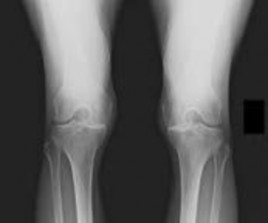

Question 11:

A 14-year-old female presents for operative evaluation of adolescent idiopathic scoliosis. Standing full-length spine radiographs show a main thoracic curve of 55 degrees and a lumbar curve of 35 degrees. The proximal thoracic curve is 20 degrees. On side-bending radiographs, the main thoracic curve corrects to 30 degrees, the lumbar curve corrects to 15 degrees, and the proximal thoracic curve corrects to 5 degrees. Based on the Lenke classification, what is the correct curve type?

Correct Answer: Type 1 (Main Thoracic)

Explanation:

In the Lenke classification system, a curve is considered structural if it fails to correct to < 25 degrees on side-bending radiographs or has an associated regional kyphosis > +20 degrees. Here, the lumbar curve corrects to 15 degrees (non-structural) and the proximal thoracic corrects to 5 degrees (non-structural). The main thoracic curve is the major curve (largest magnitude, 55 degrees). A major main thoracic curve with non-structural minor curves is classified as a Lenke Type 1.